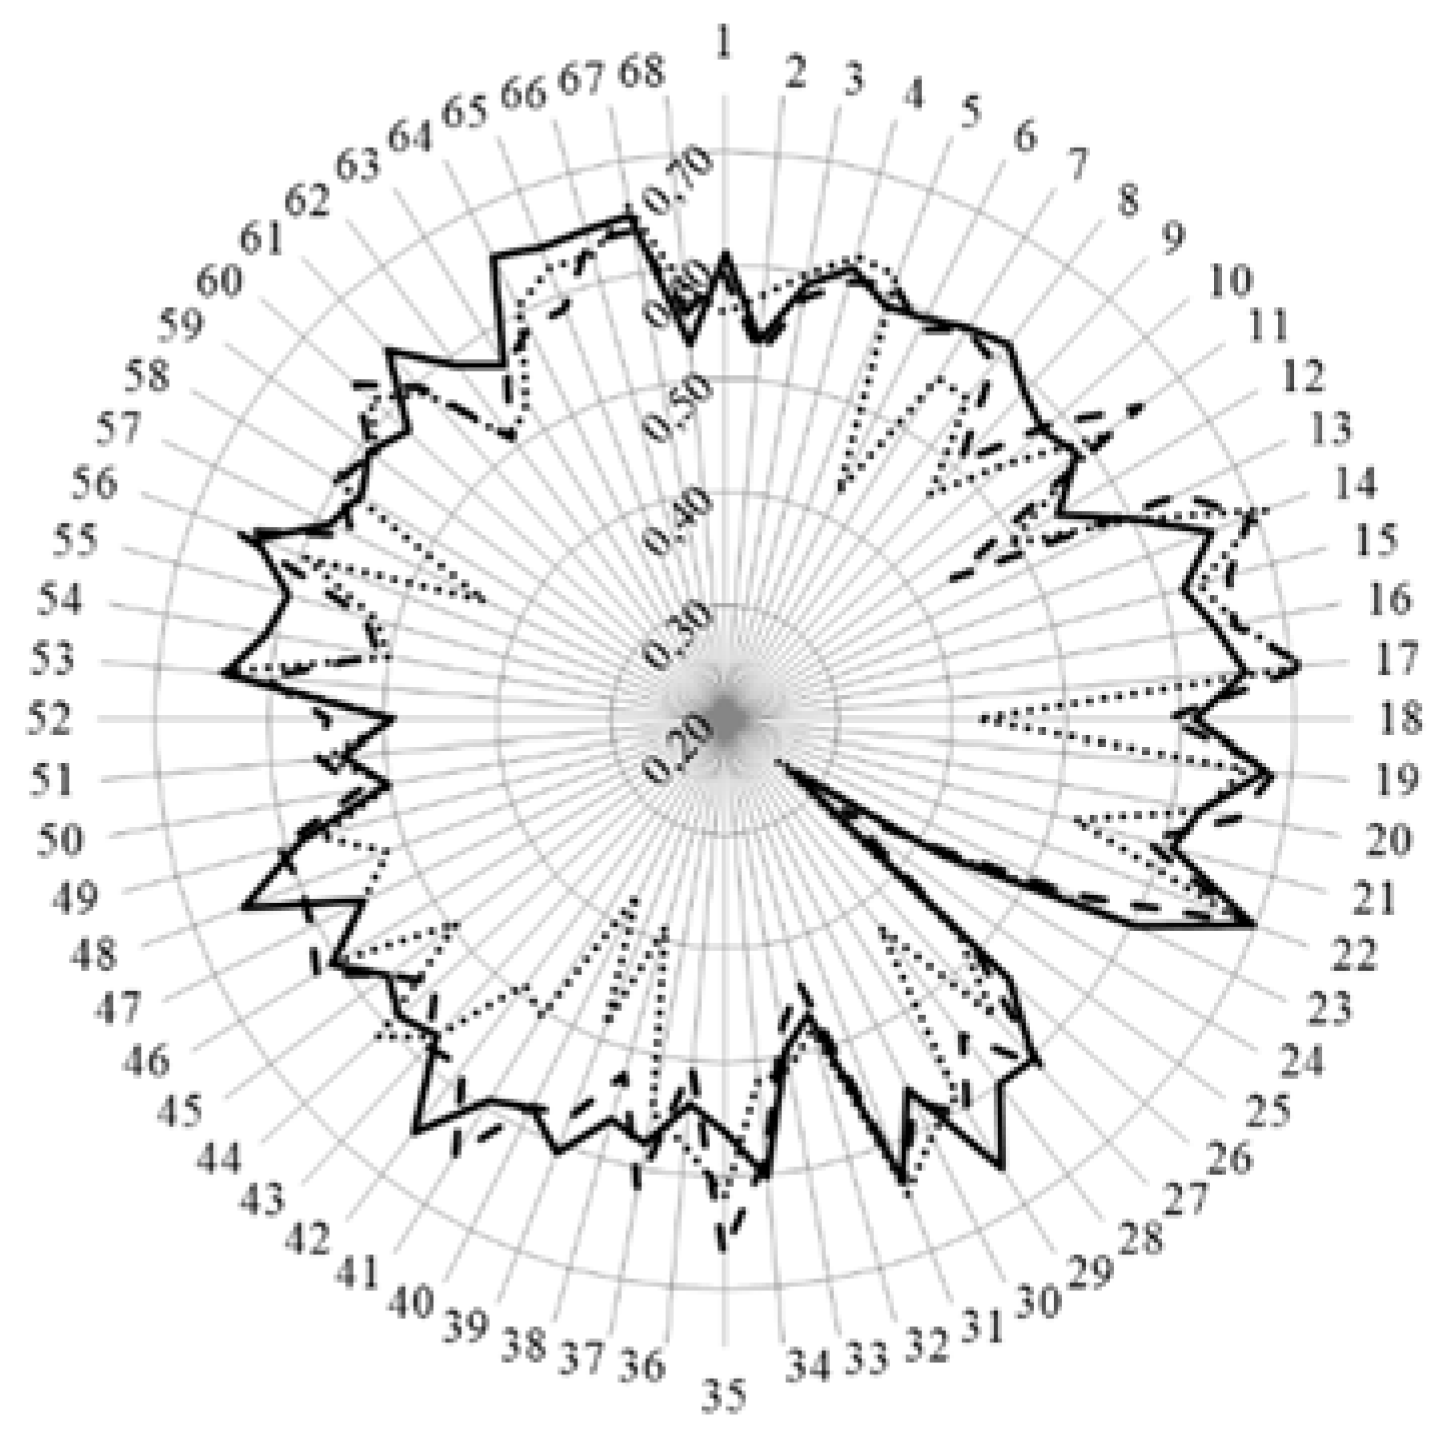

- < 0.2 poor,

- 0.21 – 0.4 fair,

- 0.41 – 0.6 moderate,

- 0.61 – 0.8 substantial,

- > 0.81 good.

3. Results and Discussion

| Cluster 7. Personal competences: learning and knowledge. | 1 | Ability to identify learning needs and to learn independently (including continuous professional development (CPD)). | 84.5 | 93.7 | 15.7 | 89.8 | 13.1 |

| 2 | Analysis: ability to apply logic to problem solving, evaluating pros and cons and following up on the solution found. | 88.8 | 94.5 | 7.5 | 91.1 | 3.6 | |

| 3 | Synthesis: capacity to gather and critically appraise relevant knowledge and to summarise the key points. | 85.1 | 92.8 | 10.8 | 87.9 | 4.0 | |

| 4 | Capacity to evaluate scientific data in line with current scientific and technological knowledge. | 76.5 | 87.3 | 18.5 | 75.8 | 0.4 | |

| 5 | Ability to interpret preclinical and clinical evidence-based medical science and apply the knowledge to pharmaceutical practice. | 86.0 | 81.2 | 5.2 | 75.9 | 17.3 | |

| 6 | Ability to design and conduct research using appropriate methodology. | 60.6 | 65.4 | 4.9 | 40.2 | 34.3 | |

| 7 | Ability to maintain current knowledge of relevant legislation and codes of pharmacy practice. | 81.7 | 86.3 | 3.3 | 91.7 | 25.7 | |

| Cluster 8. Personal competences: values. | 8 | Demonstrate a professional approach to tasks and human relations. | 86.6 | 91.5 | 7.7 | 94.5 | 23.3 |

| 9 | Demonstrate the ability to maintain confidentiality. | 85.4 | 92.3 | 22.8 | 95.3 | 50.6 | |

| 10 | Take full personal responsibility for patient care and other aspects of one’s practice. | 84.4 | 88.3 | 3.2 | 94.8 | 24.9 | |

| 11 | Inspire the confidence of others in one’s actions and advice. | 77.8 | 83.8 | 8.9 | 88.8 | 13.0 | |

| 12 | Demonstrate high ethical standards. | 85.3 | 95.3 | 43.4 | 95.2 | 24.6 | |

| Cluster 9. Personal competences: communication and organisational skills. | 13 | Effective communication skills (both orally and written). | 91.2 | 93.5 | 3.9 | 94.8 | 4.0 |

| 14 | Effective use of information technology. | 81.1 | 83.8 | 1.4 | 86.1 | 3.8 | |

| 15 | Ability to work effectively as part of a tea. | 86.4 | 83.3 | 6.1 | 89.2 | 1.1 | |

| 16 | Ability to identify and implement legal and professional requirements relating to employment (e.g., for pharmacy technicians) and to safety in the workplace. | 74.8 | 77.9 | 1.9 | 81.0 | 4.5 | |

| 17 | Ability to contribute to the learning and training of staff. | 73.5 | 79.6 | 6.6 | 82.5 | 6.6 | |

| 18 | Ability to design and manage the development processes in the production of medicines. | 61.2 | 60.0 | 0.8 | 43.2 | 38.0 | |

| 19 | Ability to identify and manage risk and quality of service issues. | 77.5 | 76.1 | 4.0 | 79.2 | 2.3 | |

| 20 | Ability to identify the need for new services. | 65.0 | 61.8 | 7.7 | 64.5 | 1.2 | |

| 21 | Ability to communicate in English and/or locally relevant languages. | 84.5 | 79.6 | 2.3 | 74.1 | 16.3 | |

| 22 | Ability to evaluate issues related to quality of service. | 73.0 | 71.0 | 3.5 | 77.9 | 7.4 | |

| 23 | Ability to negotiate, understand a business environment and develop entrepreneurship. | 62.2 | 46.4 | 15.6 | 64.1 | 2.0 | |

| Cluster 10. Personal competences: knowledge of different areas of the science of medicines. | 24 | Plant and animal biology. | 38.8 | 31.1 | 5.1 | 39.3 | 1.0 |

| 25 | Physics. | 20.9 | 25.6 | 2.3 | 21.7 | 0.8 | |

| 26 | General and inorganic chemistry | 53.0 | 45.6 | 3.3 | 43.9 | 5.3 | |

| 27 | Organic and medicinal/pharmaceutical chemistry. | 86.3 | 80.2 | 10.8 | 66.0 | 37.0 | |

| 28 | Analytical chemistry | 65.8 | 60.0 | 3.0 | 41.9 | 46.9 | |

| 29 | General and applied biochemistry (medicinal and clinical). | 85.4 | 74.2 | 10.8 | 68.8 | 22.6 | |

| 30 | Anatomy and physiology; medical terminology. | 85.2 | 75.8 | 11.2 | 88.7 | 3.3 | |

| 31 | Microbiology. | 72.2 | 67.0 | 3.3 | 72.2 | 1.5 | |

| 32 | Pharmacology including pharmacokinetics. | 97.5 | 95.6 | 3.7 | 94.7 | 3.0 | |

| 33 | Pharmacotherapy and pharmaco-epidemiology. | 95.3 | 92.5 | 3.1 | 94.3 | 2.2 | |

| 34 | Pharmaceutical technology including analyses of medicinal products. | 86.9 | 89.0 | 1.4 | 62.0 | 50.8 | |

| 35 | Toxicology. | 85.0 | 84.4 | 17.3 | 74.0 | 27.7 | |

| 36 | Pharmacognosy. | 65.9 | 52.9 | 11.3 | 66.5 | 2.1 | |

| 37 | Legislation and professional ethics. | 71.7 | 88.8 | 26.8 | 89.5 | 44.2 | |

| Cluster 11. Personal competences: understanding of industrial pharmacy. | 38 | Current knowledge of design, synthesis, isolation, characterisation and biological evaluation of active substances. | 59.9 | 57.5 | 1.9 | 41.7 | 34.2 |

| 39 | Current knowledge of good manufacturing practice (GMP) and of good laboratory practice (GLP). | 79.2 | 75.4 | 1.6 | 59.4 | 29.8 | |

| 40 | Current knowledge of European directives on qualified persons (QPs). | 55.3 | 59.2 | 1.8 | 43.7 | 39.9 | |

| 41 | Current knowledge of drug registration, licensing and marketing. | 65.7 | 72.1 | 4.6 | 55.7 | 11.9 | |

| 42 | Current knowledge of good clinical practice (GCP). | 78.1 | 68.2 | 9.1 | 64.5 | 23.8 | |

| Cluster 12. Patient care competences: patient consultation and assessment. | 43 | Ability to perform and interpret medical laboratory tests. | 72.0 | 65.3 | 5.9 | 65.5 | 6.0 |

| 44 | Ability to perform appropriate diagnostic or physiological tests to inform clinical decision making e.g., measurement of blood pressure. | 76.1 | 64.5 | 17.3 | 73.6 | 7.8 | |

| 45 | Ability to recognise when referral to another member of the healthcare team is needed because a potential clinical problem is identified (pharmaceutical, medical, psychological or social). | 91.7 | 89.1 | 2.2 | 91.7 | 9.5 | |

| Cluster 13. Patient care competences: need for drug treatment. | 46 | Retrieval and interpretation of relevant information on the patient’s clinical background. | 85.6 | 79.3 | 8.4 | 84.0 | 0.7 |

| 47 | Retrieval and interpretation of an accurate and comprehensive drug history if and when required. | 87.6 | 89.4 | 5.1 | 91.5 | 2.3 | |

| 48 | Identification of non-adherence and implementation of appropriate patient intervention. | 87.1 | 85.8 | 6.1 | 86.8 | 24.5 | |

| 49 | Ability to advise to physicians and—in some cases—prescribe medication. | 81.9 | 80.7 | 2.5 | 87.6 | 5.3 | |

| Cluster 14. Patient care competences: drug interactions. | 50 | Identification, understanding and prioritisation of drug-drug interactions at a molecular level (e.g., use of codeine with paracetamol). | 91.4 | 91.8 | 1.1 | 91.6 | 0.6 |

| 51 | Identification, understanding, and prioritisation of drug-patient interactions, including those that preclude or require the use of a specific drug (e.g., trastuzumab for treatment of breast cancer in women with HER2 overexpression). | 91.4 | 87.7 | 4.4 | 89.7 | 5.0 | |

| 52 | Identification, understanding, and prioritisation of drug-disease interactions (e.g., NSAIDs in heart failure). | 97.0 | 94.5 | 8.9 | 96.6 | 2.7 | |

| Cluster 15. Patient care competences: provision of drug product. | 53 | Familiarity with the bio-pharmaceutical, pharmacodynamic and pharmacokinetic activity of a substance in the body. | 89.3 | 90.8 | 3.5 | 81.2 | 11.6 |

| 54 | Supply of appropriate medicines taking into account dose, correct formulation, concentration, administration route and timing. | 94.3 | 96.3 | 16.3 | 94.9 | 18.0 | |

| 55 | Critical evaluation of the prescription to ensure that it is clinically appropriate and legal. | 93.9 | 94.1 | 6.6 | 94.0 | 11.1 | |

| 56 | Familiarity with the supply chain of medicines and the ability to ensure timely flow of drug products to the patient. | 81.6 | 78.6 | 4.5 | 84.6 | 11.3 | |

| 57 | Ability to manufacture medicinal products that are not commercially available. | 74.1 | 69.0 | 1.5 | 60.5 | 21.2 | |

| Cluster 16. Patient care competences: patient education. | 58 | Promotion of public health in collaboration with other actors in the healthcare system. | 75.8 | 75.1 | 1.1 | 82.6 | 5.9 |

| 59 | Provision of appropriate lifestyle advice on smoking, obesity, etc. | 76.9 | 71.0 | 3.8 | 80.9 | 4.7 | |

| 60 | Provision of appropriate advice on resistance to antibiotics and similar public health issues. | 90.3 | 89.4 | 5.2 | 93.1 | 3.6 | |

| Cluster 17. Patient care competences: provision of information and service. | 61 | Ability to use effective consultations to identify the patient’s need for information. | 85.6 | 81.1 | 3.1 | 90.9 | 11.1 |

| 62 | Provision of accurate and appropriate information on prescription medicines. | 92.7 | 89.3 | 8.0 | 94.4 | 11.0 | |

| 63 | Provision of informed support for patients in selection and use of non-prescription medicines for minor ailments (e.g., cough remedies). | 85.7 | 89.4 | 1.7 | 94.0 | 14.4 | |

| Cluster 18. Patient care competences: monitoring of drug therapy. | 64 | Identification and prioritisation of problems in the management of medicines in a timely manner and with sufficient efficacy to ensure patient safety. | 88.5 | 87.9 | 8.2 | 93.0 | 8.7 |

| 65 | Ability to monitor and report to all concerned in a timely manner, and in accordance with current regulatory guidelines on Good Pharmacovigilance Practices (GVPs), Adverse Drug Events and Reactions (ADEs and ADRs). | 79.8 | 80.9 | 5.0 | 83.4 | 3.3 | |

| 66 | Undertaking of a critical evaluation of prescribed medicines to confirm that current clinical guidelines are appropriately applied. | 80.7 | 81.6 | 0.3 | 80.6 | 4.5 | |

| Cluster 19. Patient care competences: evaluation of outcomes. | 67 | Assessment of outcomes on the monitoring of patient care and follow-up interventions. | 73.3 | 73.7 | 0.5 | 79.0 | 4.4 |

| 68 | Evaluation of cost effectiveness of treatment. | 53.3 | 57.7 | 2.1 | 61.2 | 4.8 |